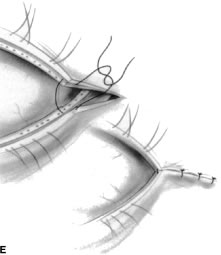

The tarsus provides the primary support or foundation for the eyelids. Although degeneration of the tarsus may promote eyelid laxity,3 the principle focus of weakness of the eyelids is at the lateral and medial canthal tendons.4 Jones and Wobig5 described the medial canthal tendon with a prominent anterior component firmly connecting the medial canthal angle to the maxillary process of the frontal bone. The posterior limb of the medial canthal tendon provides deep support to the posterior lacrimal crest. Anderson6 also emphasized the role of a superior branch of the medial canthal tendon to support the canthal angle. Gioia and coworkers7 have provided a clear description of lateral canthal anatomy. The lateral canthal tendon has contributions from the lateral aspects of the tarsus and the preseptal and pretarsal orbicularis muscle; these insert on the inner aspect of the lateral orbital rim at Whitnall's (lateral orbital) tubercle. The posterior deep insertion of the lateral canthal tendon allows the lateral aspect of the eyelids to approximate the globe.

Ectropion and entropion share similar anatomic features. The most common predisposing anatomic factors for lower lid malpositions are horizontal eyelid laxity and weakness or defects of the lower lid retractors. The general weakness of the eyelid is caused by a weakness of the medial and lateral canthal tendons, permitting horizontal eyelid laxity.4 As such, it is best to consider lower eyelid laxity as resulting from laxity of the tarsoligamentous sling or support for the eyelid. The anatomic weakness can be demonstrated by the snap test. Downward retraction is exerted on the lower lid, pulling it away from the globe. On relapse, the lower lid should snap back against the globe spontaneously. Failure of the eyelid to snap back against the globe with a single blink indicates excessive laxity of the tarsoligamentous sling.

The lower eyelid retractors may be weakened or may actually become disinserted from the inferior tarsal border. Weakness or defect of the lower eyelid retractors creates in an instability of the inferior tarsal border that is manifested clinically as ectropion or entropion.